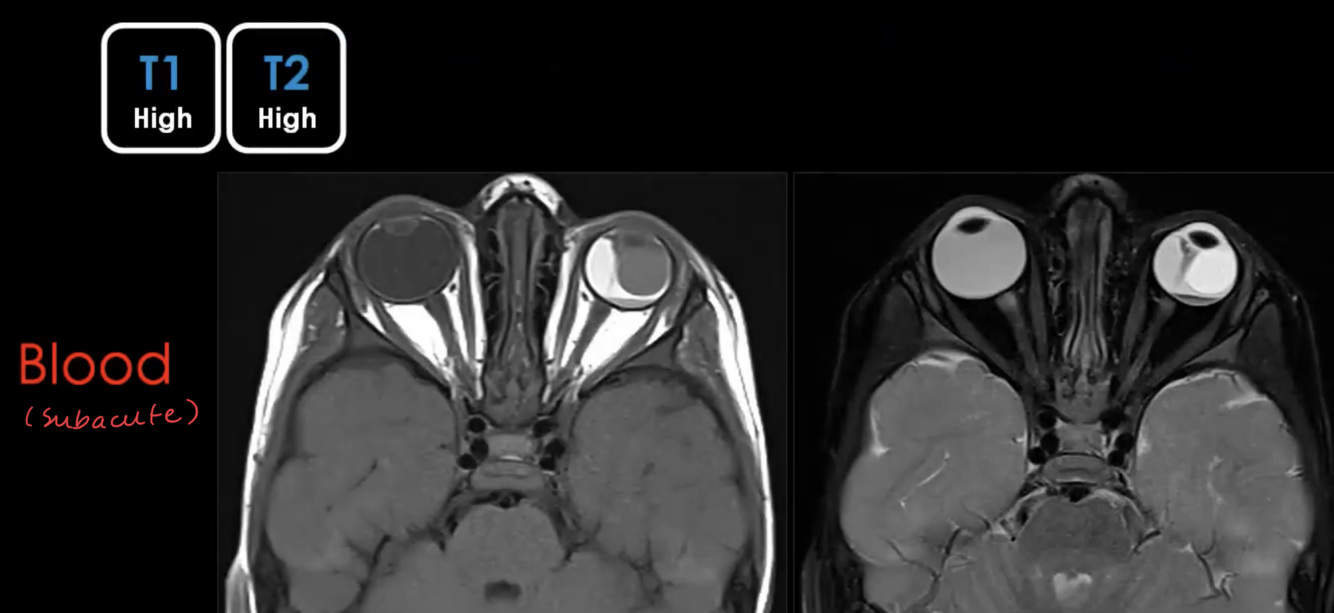

What is HIGH T1 / HIGH T2?